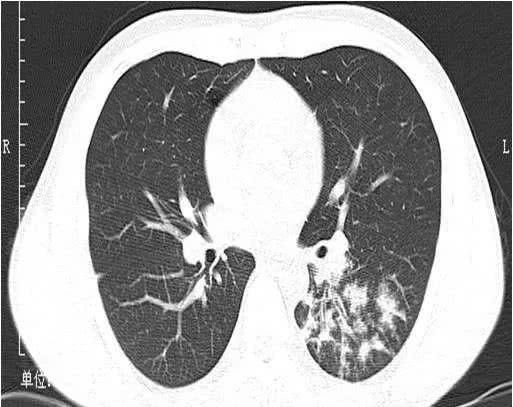

该名女孩脸上前额上长了一个疖肿,以为把疖肿挤出就会好,结果用力挤压后,造成眼眶感染,细菌进入血液循环,在血液内大量繁殖,引起了败血症。除了发烧之外,这些毒力很强的金黄色葡萄球菌种植到了肺部,引起了十几个空洞。